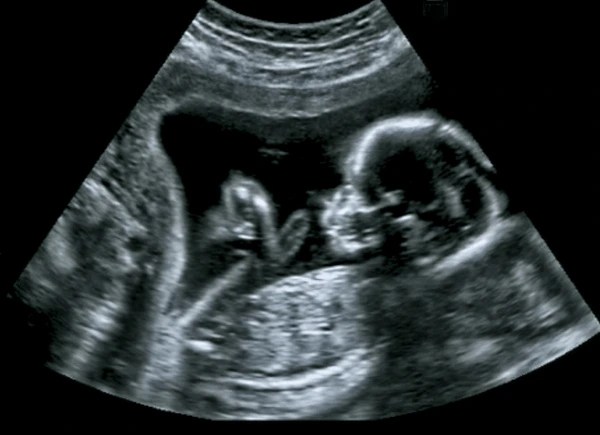

I’m not interested in loading guilt and condemnation upon anyone; Satan is the accuser. However, for all who have no background or knowledge of Christian faith or Scripture, I would offer that it provides freedom from the lies and snare that is abortion. The propaganda media suggest it is merely a choice to end the life of an unborn baby, that there is no baby, but a mass of inert tissue. Science refutes these lies – six weeks after conception a heart beat is detectible; at eight weeks brain activity is detectible. Much more life can be observed as the baby grows and sooner as science improves its methods.